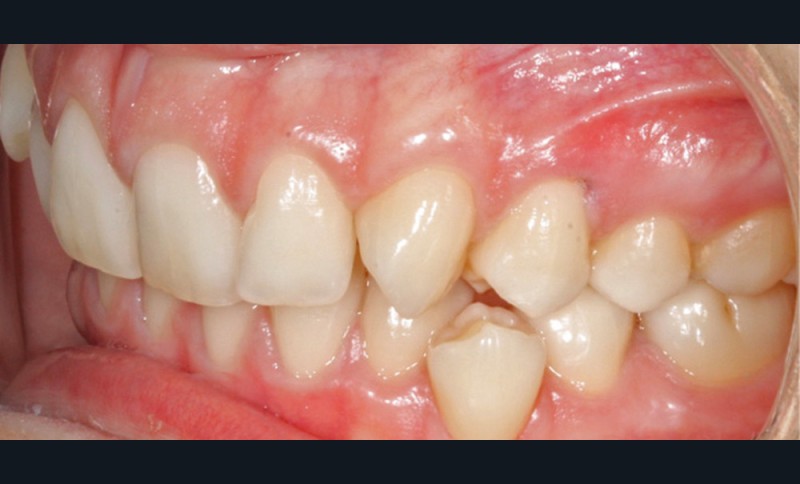

L’examen intra-arcade met en évidence une hygiène bucco-dentaire irréprochable, favorable à un traitement en technique linguale. Le phénotype parodontal est fin dans la région incisivo-canine mandibulaire. L’encombrement est estimé à 8 mm à la mandibule et à 4 mm au maxillaire (fig. 1). Les arcades ont des formes similaires, en U. Les rapports inter-arcades mettent en évidence une classe 1 d’Angle molaire, une classe 2 d’Angle canine et une supraclusion antérieure (recouvrement : 5 mm ; surplomb diminué). Les milieux inter-incisifs sont déviés entre eux avec une origine mixte (= 1,5 mm) (fig. 2).